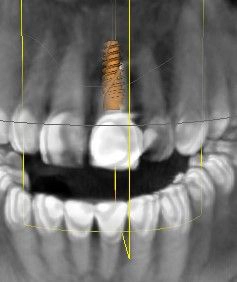

Diagnostik und Planung

In Vorbereitung auf die Implantatplanung und das CAD/CAM-Herstellen der temporären Krone erfolgte eine digitale Datenerfassung mit dem Intraoralscanner (Trios 3, 3Shape). Der Datensatz der Ausgangssituation sollte später bei der CAD-Konstruktion hilfreiche Informationen liefern (Abb. 3). Mit dem Scan ist die Ausgangssituation digital archiviert und steht jederzeit zum Abruf bereit. Zudem wurde ein DVT für die Planung der Implantatposition am dreidimensionalen Bild vorgenommen und der DICOM-Datensatz in die Implantatplanungssoftware importiert (Abb. 4 und 5).

Theoretisch kann in der Planungssoftware der STL-Datensatz aus dem Intraoralscanner (Ausgangssituation oder Set-up) hinzugezogen und so die Implantatposition aus prothetischer Sicht ideal definiert werden. Im vorgestellten Fall ergab die 3D-Diagnostik ein ausreichend stabiles Knochenvolumen in regio 21. Geplant worden ist die Insertion eines BLX-Implantates (Straumann).